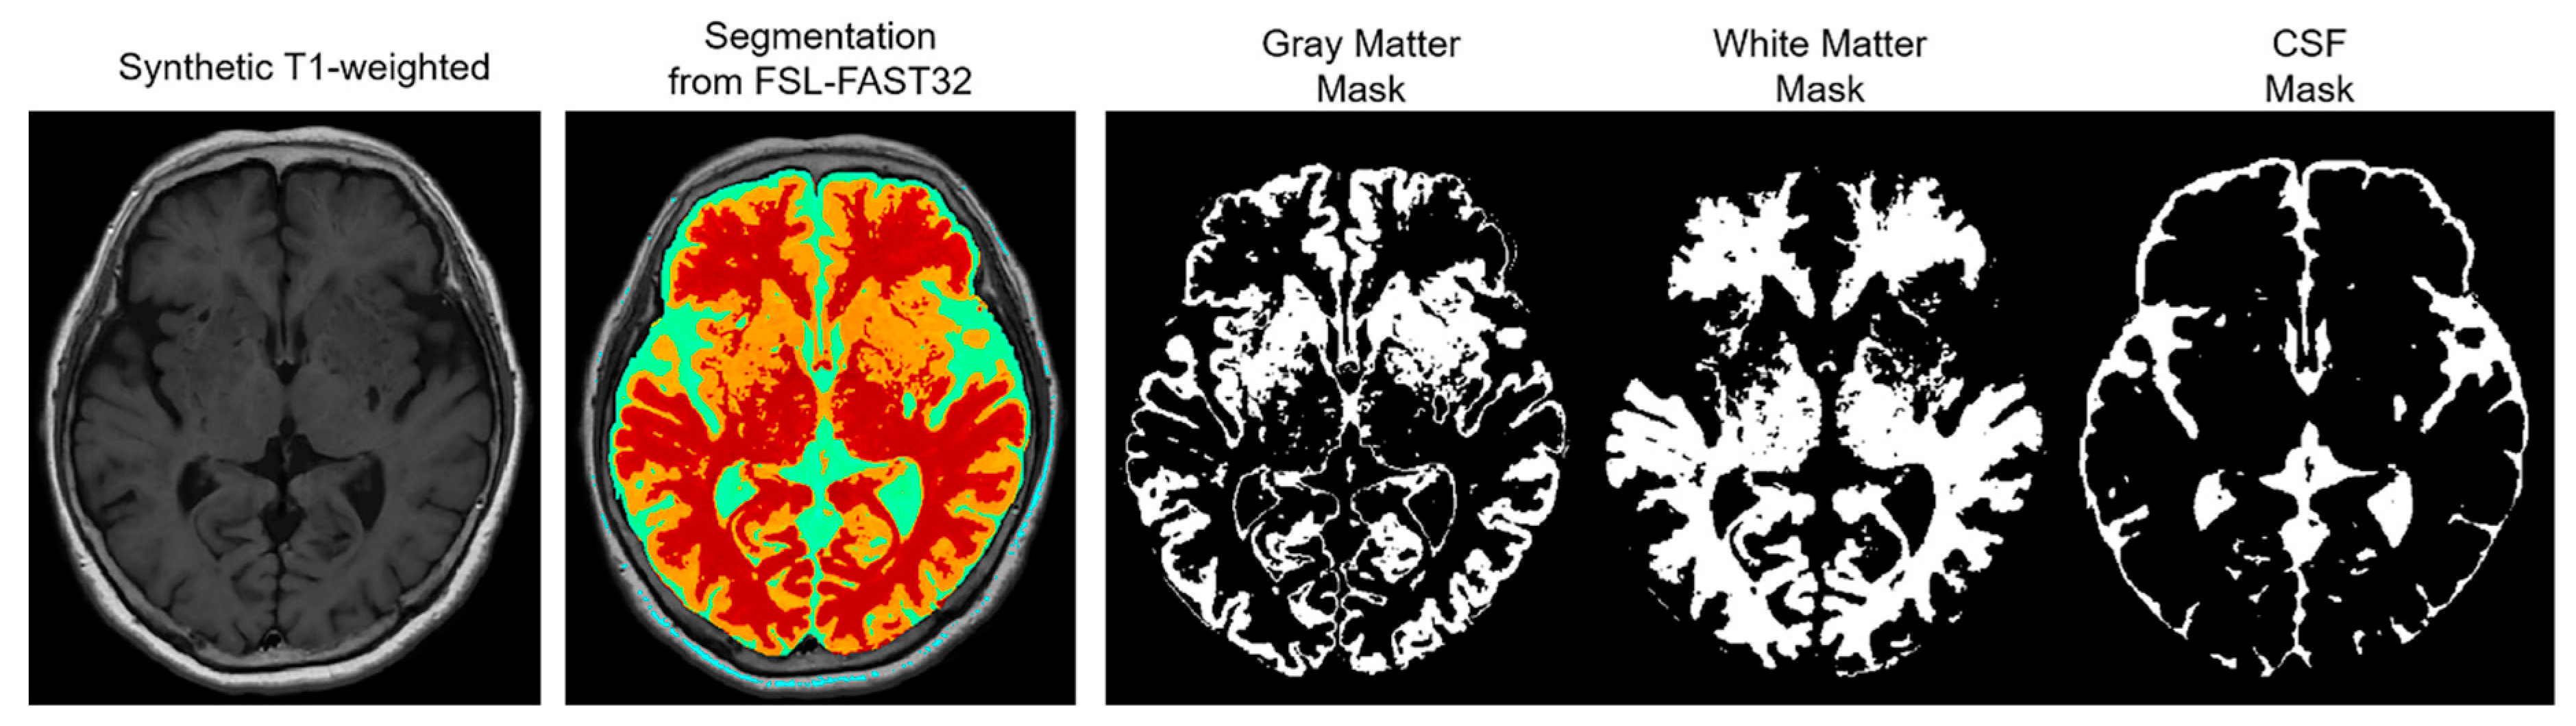

The NRMSE and PSNR were compared based on three automatically segmented regions as follows: gray matter (GM), white matter (WM), and CSF. This region-wise evaluation was conducted to indicate which region was most improved, and the segmentations for the regions were retrieved via segmentation with FSL-FAST32 using the synthetic T1-weighted images (

Figure 1).